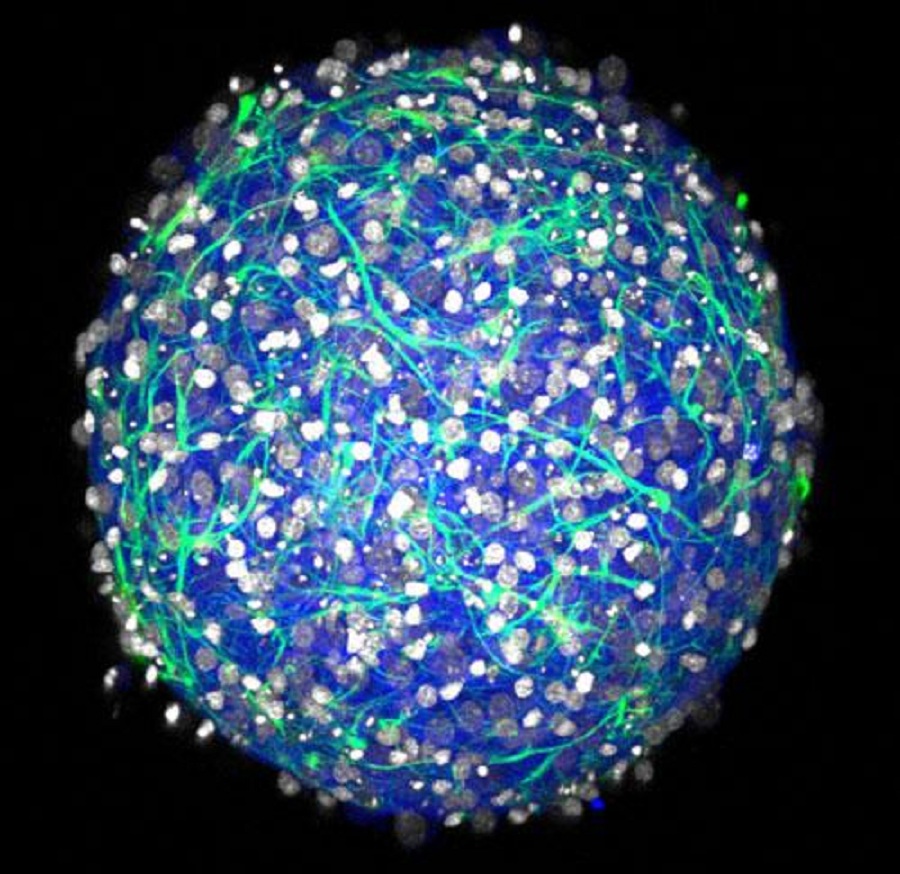

Los investigadores han creado minicerebros de neuronas. Imagen: Laboratorio Hoffman-Kim. Fuente: Universidad de Brown.

Las pequeñas bolas de cerebro de Brown no realizan ninguna reflexión, pero producen señales eléctricas y forman sus propias conexiones neuronales -sinapsis-, lo que las convierte en bancos de pruebas fácilmente fabricables para la investigación en neurociencias, dicen los autores.

Las esferas de tejido cerebral comienzan a formarse en el plazo de un día desde que los cultivos se siembran y forman complejas redes neuronales 3D en unas dos o tres semanas, muestra el trabajo.

-Diversos tipos de células: los cultivos contienen tanto neuronas inhibidoras como excitadoras y diversas variedades de células neuronales de apoyo esenciales llamadas células gliales.

-Eléctricamente activo: las neuronas se disparan y forman conexiones sinápticas, produciendo redes complejas.

-3-D: Las células se conectan y comunican dentro de una geometría realista, en lugar de simplemente a través de una superficie plana como en un cultivo 2D.

-Densidad natural: Los experimentos mostraron que los mini-cerebros tienen una densidad de unos pocos cientos de miles de células por milímetro cúbico, que es similar a la de un cerebro de roedor natural.

-Estructura física: Las células del mini-cerebro producen su propia matriz extracelular, produciendo un tejido con las mismas propiedades mecánicas (blandura) que el tejido natural. Además los cultivos no se basan en materiales extraños tales como andamios de colágeno.